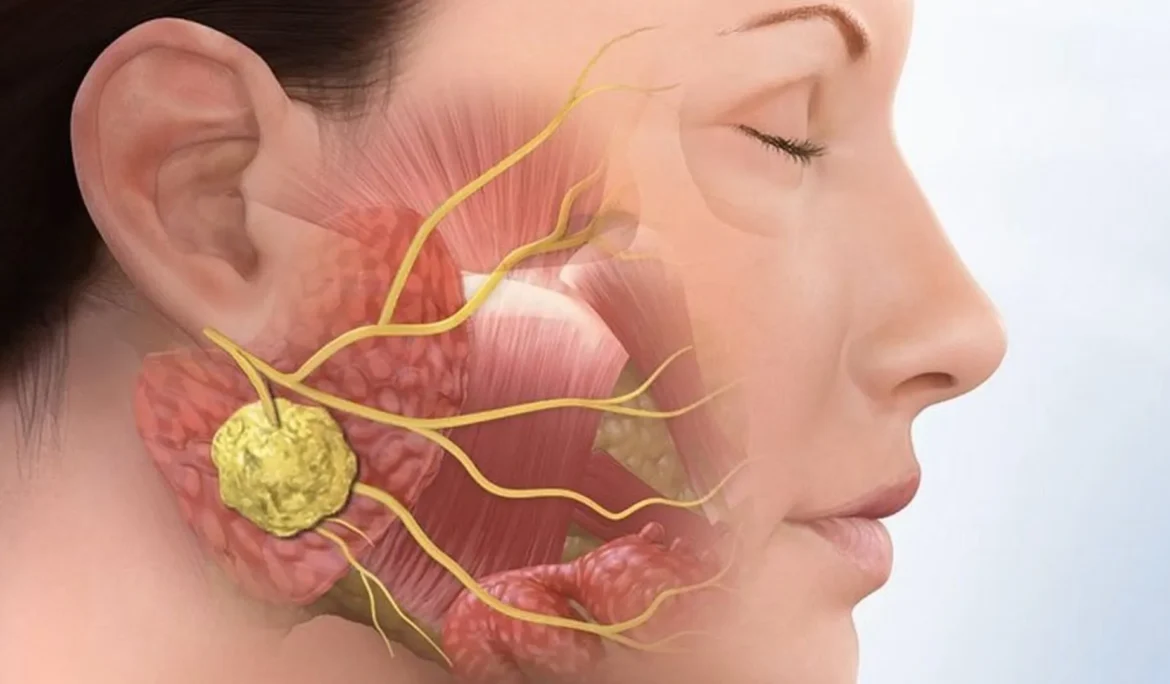

Răng số 3 (răng nanh) giữ vai trò quan trọng trong thẩm mỹ khuôn mặt và chức năng khớp cắn. Khi răng này mọc ngầm, nó không

Câu hỏi ” răng mọc ngầm có cần nhổ không?” luôn là nỗi băn khoăn lớn của nhiều người. Liệu tất cả các răng mọc ngầm đều

Nụ cười khỏe đẹp không chỉ nằm ở những chiếc răng trắng sáng, mà còn phụ thuộc vào sức khỏe vững vàng của cả cấu trúc xương